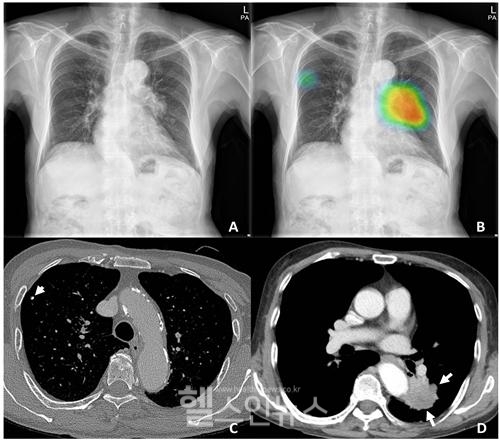

아래 그림은 인공지능(AI) 솔루션이 어떻게 의료진이 놓칠 수 있는 중요한 세부사항을 찾아내는지 보여준다.

AI는 좌측 폐 중간 부위에 있는 종괴와 우측 폐 중간 부위에 있는 작은 결절을 정확하게 감지하여 화살표로 표시했다. 기존의 방식으로는 이러한 병변을 놓칠 수 있지만, AI는 높은 정확도로 이들을 찾아내어 의사들이 더 빠르고 정확하게 진단할 수 있도록 도와준다. 이러한 기술 덕분에 환자는 더 신속한 치료를 받을 수 있고, 의료진은 보다 정확한 정보를 바탕으로 최적의 치료 계획을 세울 수 있다.